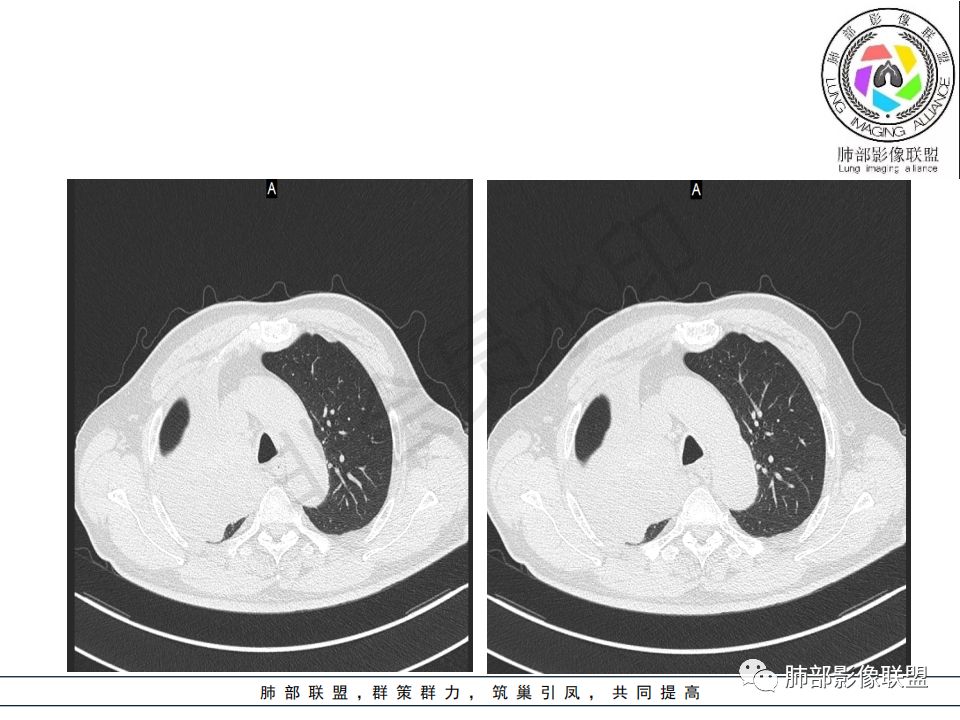

影像:影像右侧大支气管阻塞,临床没有症状或很轻微,要想到胃腺癌转移;胸壁代偿好,透亮度稍低不明显,慢性过程;34.8-52.5HU,主病灶支气管前壁另有1结节,都做成增强两期了,动脉期较平扫有强化;

诊断:多发,转移,无淋巴结及胸腔积液;

晨读病例:老年男性,症状轻,右侧胸廓略塌陷,右肺主支气管内外软组织影,支气管变窄截断,右肺上叶不张,其内见细砂样钙化,周围看见小结节,右肺门看见一淋巴结稍大,增强不均匀强化,胃癌病史,常规考虑:转移,或原发肺恶性鳞癌。鉴别支气管TB?

从强化情况和冠状位看主要还是从外向内的一个肿块,有不张,但不张范围不大,近端支气管堵塞,考虑腺癌或类癌(原发或转移都可能),鉴别鳞癌。

先转移到支气管壁上淋巴管

然后突破粘膜

本质上还是血行淋巴转移

@刘鋆(福州长乐区医院)影像科 转移啊,腔外都在生长,部分通过支气管壁进入腔内

@刘鋆(福州长乐区医院)影像科 先转移生长到外面,然后进入腔内生长,也是外朝内一种,与平时那种外朝内生长逐渐侵犯近端气管没有太多区别,只不过这个是转移而已。

病理结果:腺癌,考虑来源消化道

1.右肺上叶较大块影,密度不均,轻度强化并见低密度区,所属支气管截断并腔内突入,是符合肺鳞癌的影像学特征和生物学行为的。

2.胃癌常会首先胃旁淋巴结、腹主动脉淋巴结转移,肝脏血行转移,以及双肺多发转移,本例孤立右肺上叶病灶巨大,多有不符。

3.胃癌多血供,患者肺内病灶轻度强化。